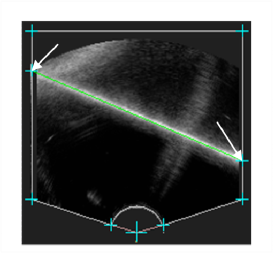

Refer to caption

Figure 4: Screenshot of a successful automatic plane extraction. Note that lines are correctly detected in spite of a degraded membrane image caused by a steep scan angle. The arrows point at the line intersections with the mask.